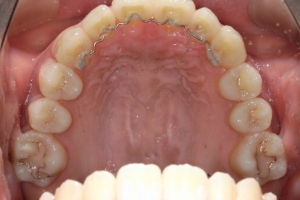

BEFORE

治療前

PROCESS

半年

AFTER

治療後

下の前歯が上あごの歯ぐきに当たるほど噛み合わせが深く、そのことが原因で上顎歯列の正中にすき間(正中離開)が生じていました。部分矯正ですき間を無理やり閉じても、噛み合わせが深いままでは治療後の再発リスクが高くなります。そのため全体矯正で奥歯の噛み合わせを整え、噛み合わせを浅くしつつ前歯を並べました。正中離開は戻りやすい傾向があるので、再発を防ぐため固定式リテーナーを推奨しています。